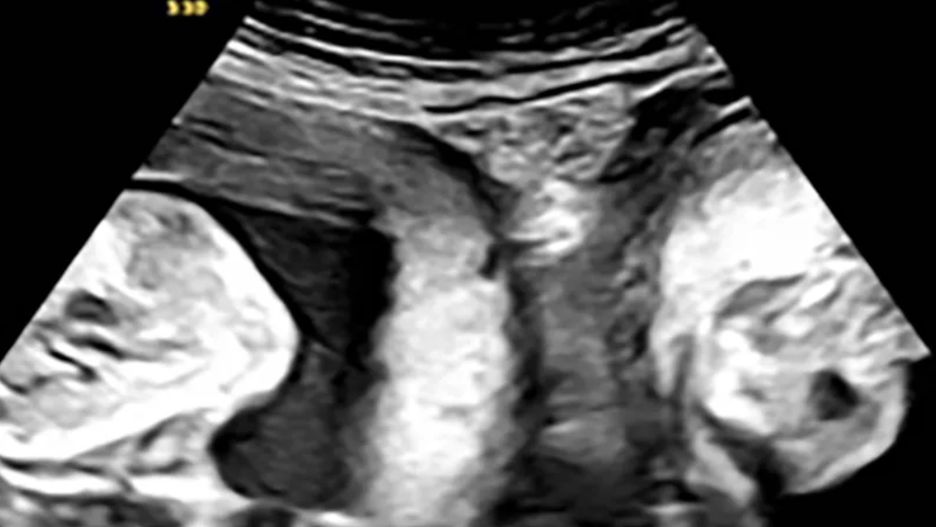

W północno-zachodnich Chinach doszło do niezwykłego wydarzenia, które przyciągnęło uwagę milionów użytkowników mediów społecznościowych. Kobieta cierpiąca na rzadką wadę anatomiczną urodziła bliźnięta, które rozwijały się w dwóch oddzielnych macicach. Zdaniem lekarzy, taki przypadek to prawdziwa rzadkość.

Matka, zidentyfikowana jedynie jako Li, powitała na świecie chłopca i dziewczynkę. Dzieci przyszły na świat dzięki cesarskiemu cięciu. Poród odbył się w szpitalu w mieście Xi’an, w prowincji Shaanxi. Przedstawiciele Xi’an People’s Hospital nazwali to wydarzenie "jednym na milion".

Niezwykle rzadko zdarza się, by bliźnięta były poczęte w każdej z jam macicy, a jeszcze rzadziej, by udało się je donosić do terminu porodu –napisał 18 września szpital na swoim oficjalnym koncie w chińskim odpowiedniku platformy X, Weibo.

Li urodziła się z rzadką wadą, znaną jako macica dwurożna (uterus didelphys), która występuje u około jednej na 2000 kobiet. Polega ona na tym, że kobieta ma dwie macice oraz dwie szyjki macicy. Mimo tej niezwykłej sytuacji medycznej, udało się jej donosić obie ciąże i urodzić zdrowe dzieci.

Mimo obaw, historia Li zakończyła się szczęśliwie. Warto dodać, że w przeszłości kobieta straciła ciążę, co mogło wzbudzać niepokój podczas kolejnych prób. Jednak w styczniu tego roku, podczas wczesnego badania 3USG, Li dowiedziała się, że spodziewa się nie jednego, a dwojga dzieci – każdego w innej macicy.

Pod stałą, ścisłą opieką medyczną Li doczekała szczęśliwego rozwiązania. Chłopiec urodził się z wagą 3,35 kg, a dziewczynka ważyła 2,42 kg. Jak podkreślił szpital, był to wynik szczegółowego nadzoru lekarzy, którzy przez całą ciążę dbali o bezpieczeństwo zarówno matki, jak i dzieci.

Ta niecodzienna historia zakończyła się szczęśliwie, a narodziny bliźniąt z każdej macicy zostały uznane za jeden z najrzadszych przypadków w medycynie.